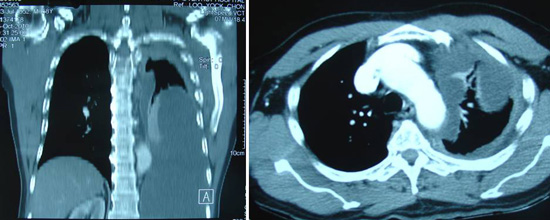

Jane (not real name) was a 47-year old lady from South Africa. She lived with her husband and their dog in a boat that sailed around the world. The happy family had been sailing like this for the past 15 years. Sometime in mid-2013, they landed in Malaysia. Jane developed breathing difficulty and was subsequently diagnosed with lung cancer. CT scan showed a 3.2 x 4.1 x 6.7 cm mass in her lung.

Bak (M952) is a 56-year-old male from Indonesia. Sometime in November 2010, he complained of itchiness but he did nothing about it. In April 2011, he went for a checkup in a hospital in Aceh, North Sumatera. He was told there was a tumour in his bile duct. On 8 April 2011, he came to Penang for further checkup. CT scan of his abdomen and pelvis indicated the following:

Bob was a 57-year-old male. In early 2010 he went to a government hospital complaining of shortness of breath. Examination indicated irregular hard swelling below the costal margin (liver area). He was jaundiced. A CT scan on 19 April 2010 indicated multiple nodules of varying sizes in both lung fields suggestive of metastases. Soft tissue nodules at the hilum – right measures 1.4 x 1.4 cm, left measures 2.3 x 2.7 cm. Enlarged liver with a 9.9 x 10.5 cm lesion in the right lobe. Multiple lesions present in both lobes of the liver. These may represent metastases.

Sujo (M858) is a 58-year-old male from Indonesia. Sometime in August 2010, he complained of breathlessness when climbing the stairs. A check up with a GP in Medan indicated fluid in his lungs.  Sujo came to a private hospital in Penang in October 2010. A CT scan indicated gross left pleural effusion associated with severe lung collapse. There was lytic lesion at T4 vertebral body associated with erosion. His liver showed fatty infiltration.